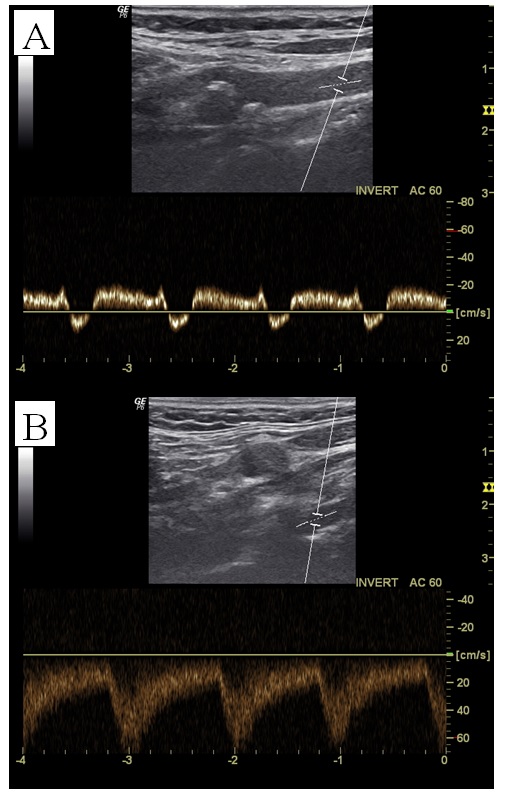

Pacjent zgłosił się do poradni chirurga naczyniowego z powodu okresowo występujących zaburzeń równowagi oraz osłabienia siły mięśniowej ręki lewej. W badaniu przedmiotowym stwierdzono podobne wyczuwanie tętna na obu tętnicach promieniowych. Różnica ciśnienia skurczowego mierzonego na obu kończynach górnych wynosiła 10 mm Hg. Pacjenta skierowano na badanie dupleksowe tętnic szyjnych i kręgowych. Oceniając tętnice szyjną wspólną (A) i kręgową (B) po stronie prawej stwierdzono obecność spektrum przedstawionego na poniższych rycinach. U pacjenta można podejrzewać: